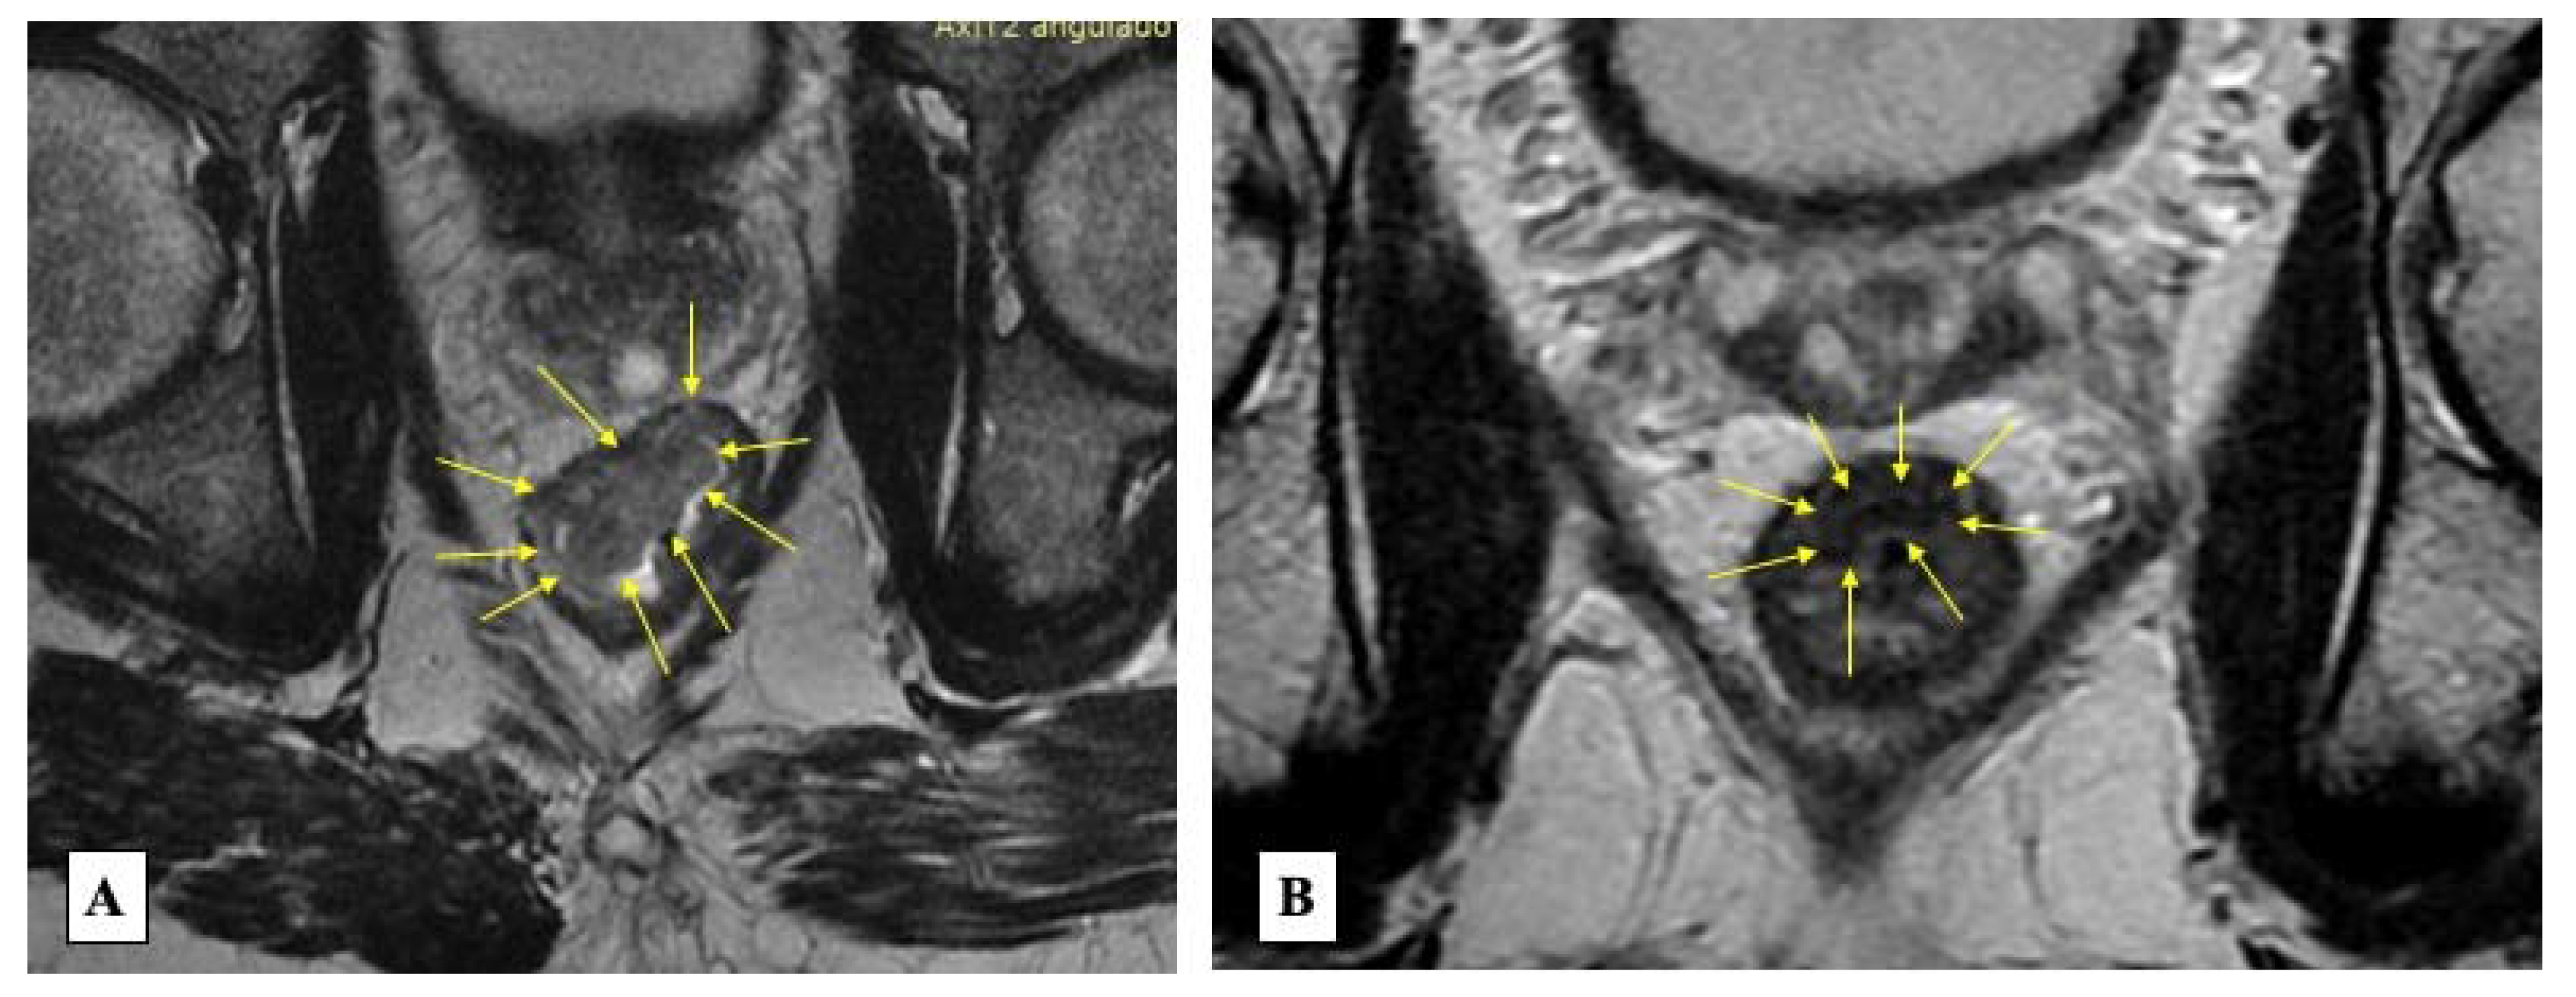

5.2. Three-Pillar Assessment Criteria

- Maas, M.; Lambregts, D.M.J.; Nelemans, P.J.; Heijnen, L.A.; Martens, M.H.; Leijtens, J.W.A.; Sosef, M.; Hulsewé, K.W.E.; Hoff, C.; Breukink, S.O.; et al. Assessment of Clinical Complete Response After Chemoradiation for Rectal Cancer with Digital Rectal Examination, Endoscopy, and MRI: Selection for Organ-Saving Treatment. Ann. Surg. Oncol. 2015, 22, 3873–3880. [Google Scholar] [CrossRef] [PubMed]

- Patel, U.; Brown, G.; Rutten, H.; West, N.; Sebag-Montefiore, D.; Glynne-Jones, R.; Rullier, E.; Peeters, M.; Van Cutsem, E.; Ricci, S.; et al. Comparison of magnetic resonance imaging and histopathological response to chemoradiotherapy in locally advanced rectal cancer. Ann. Surg. Oncol. 2012, 19, 2842–2852. [Google Scholar] [CrossRef]

- Patel, U.; Blomqvist, L.; Taylor, F.; George, C.; Guthrie, A.; Bees, N.; Brown, G. MRI after treatment of locally advanced rectal cancer: How to report tumor response--the MERCURY experience. AJR Am. J. Roentgenol. 2012, 199, W486–W495. [Google Scholar] [CrossRef] [PubMed]

- Lambregts, D.; Lahaye, M.; Heijnen, L.; Martens, M.; Maas, M.; Beets, G.; Beets-Tan, R.G. MRI and diffusion-weighted MRI to diagnose a local tumour regrowth during long-term follow-up of rectal cancer patients treated with organ preservation after chemoradiotherapy. Eur. Radiol. 2016, 26, 2118–2125. [Google Scholar] [CrossRef] [PubMed]

- Lambregts, D.; Maas, M.; Bakers, F.; Cappendijk, V.; Lammering, G.; Beets, G.; Beets-Tan, R. Long-term follow-up features on rectal MRI during a wait-and-see approach after a clinical complete response in patients with rectal cancer treated with chemoradiotherapy. Dis. Colon Rectum 2011, 54, 1521–1528. [Google Scholar] [CrossRef] [PubMed]